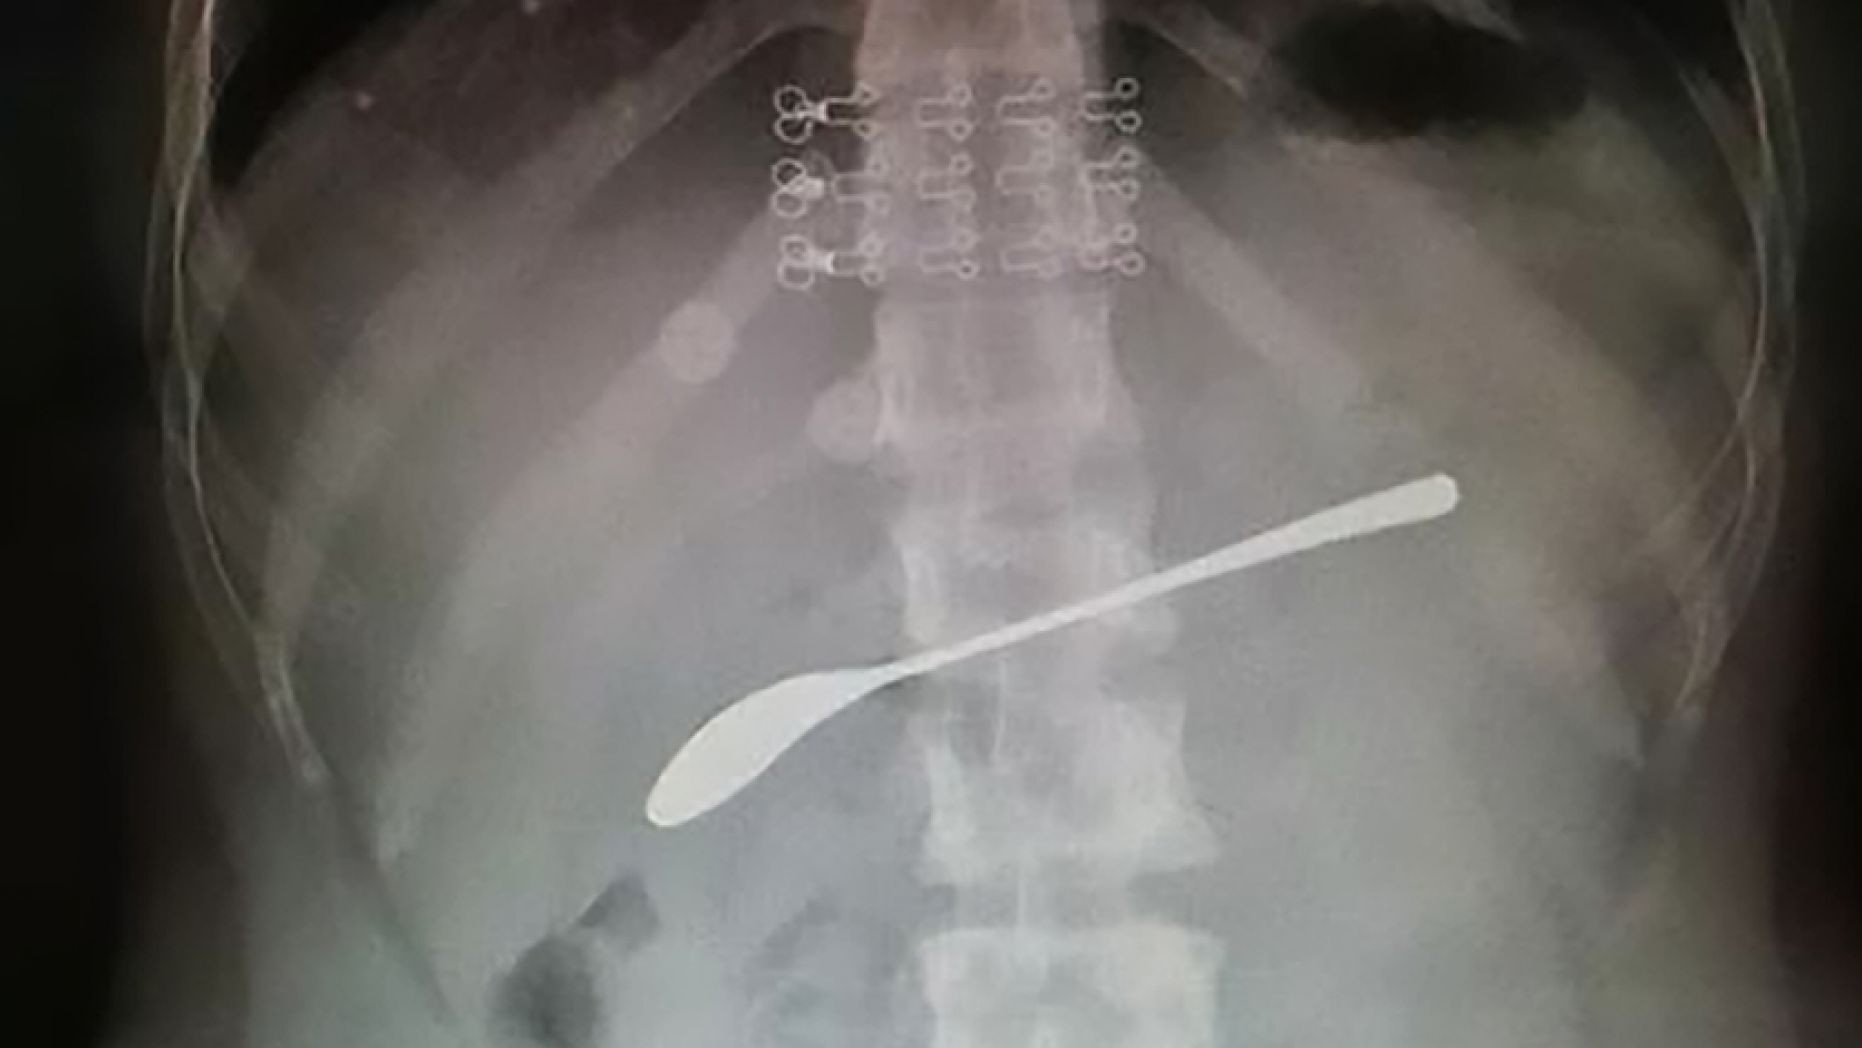

Woman got so drunk she forgot she had swallowed a 6-inch spoon, report says

The woman's doctor said that if she had waited, or ignored the pain, the spoon could?ve caused ulcers or a life-threatening infection.